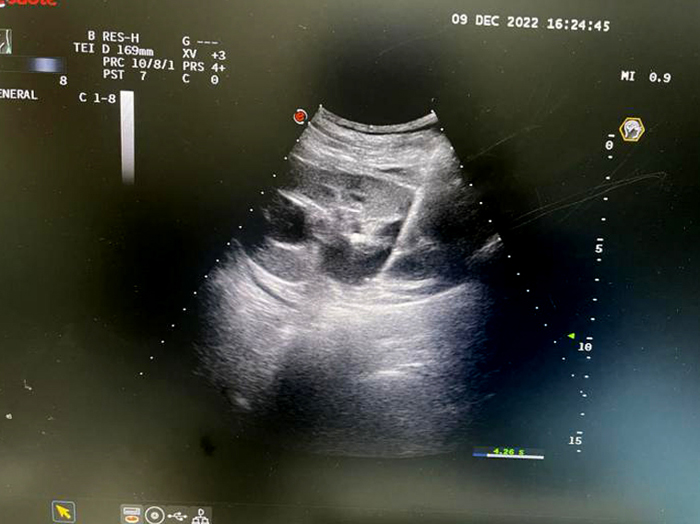

肝臟腫物微波消融術(shù)